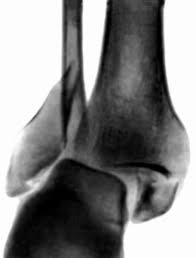

ПЕРЕЛОМ ЯКОЇ КІСТКИ І В ЯКІЙ ЇЇ ЧАСТИНІ ВИ БАЧИТЕ?

варіанти відповідей

ГОЛОВКИ HUMERUS

ДИСТАЛЬНОГО ЕПІФІЗА HUMERUS

ШИЙКИ FEMUR

ГОЛОВКИ FEMUR

ГОЛОВКИ RADIUS

ПРОКСИМАЛЬНОГО ЕПІФІЗА HUMERUS

ХІРУРГІЧНОЇ ШИЙКИ HUMERUS

АНАТОМІЧНОЇ ШИЙКИ HUMERUS